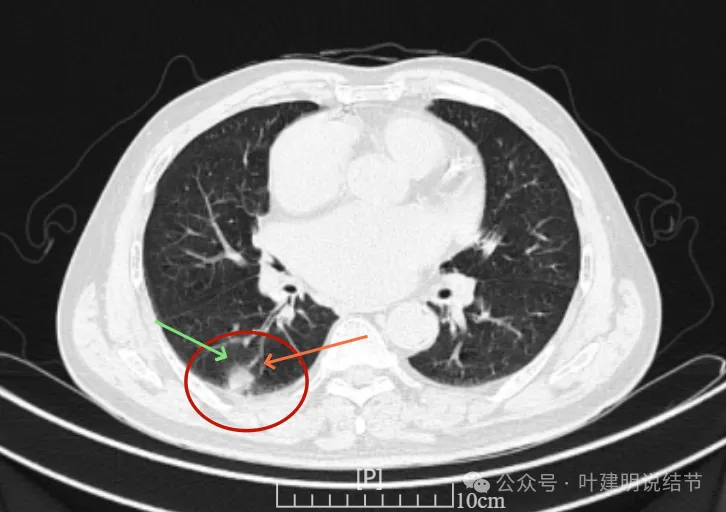

右下新增病灶,混合密度,整体轮廓较清,瘤肺边界欠清。

有小血管进入,边缘毛糙。

局部有毛刺,但不够锐利;病灶感觉有一层晕似的,邻近胸膜下也有淡磨玻璃影。

实性密度为主,周围少许很淡的磨玻璃影。

边缘不平有毛刺,但不锐利;贴着胸膜但无明显牵拉。局部表面有浅分叶似的,但总体膨胀感不够。

病灶表面不光滑,边上有晕,邻近有淡磨,贴着胸膜无牵拉。

病灶边缘欠清晰,瘤肺边界稍模糊。较宽的基底贴着胸膜。

病灶有血管进入,有浅分叶,实性为主,邻近胸膜有片状淡磨玻璃影,近胸膜无牵拉。但有一定膨胀性。

病灶实性,与血管关系较为密切。

血管走向病灶,但似乎没有被病灶影响,有向内侧的分支甚至没有哪怕一点凹向病灶侧。整体显得偏模糊。

边缘区域杂乱,边糊。